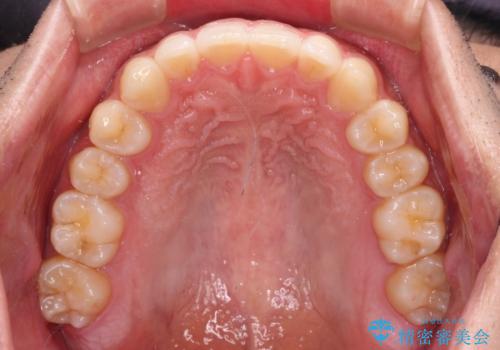

前歯のデコボコと突出感 インビザラインにて矯正治療

- 上下前歯のデコボコを気にして来院された患者様です。

インビザラインによる上下歯列の側方拡大と後方移動、IPR(歯と歯の間を削る)にるスペースの獲得により歯列を整えることとしました。

左上の小臼歯は捻転が強く、あえて180逆向きの状態で終了させる治療計画としました。